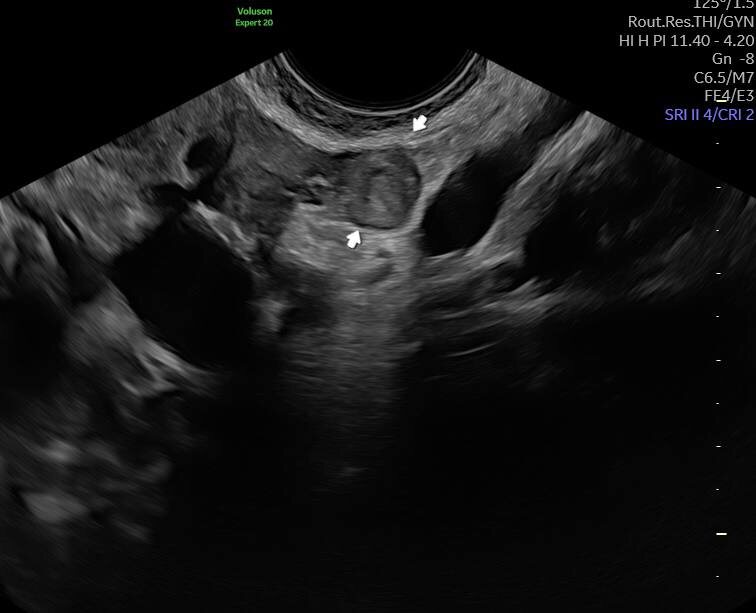

Внематочная беременность ⠀ ✅ Вчера в одной из клиник города возникло подозрение на внематочную беременность ⠀ ✅ Сегодня в «КЛИНИКА САРЕНКО»диагноз установлен ⠀ ✅ Отправил к гинекологу на лечение ⠀ 🟢 Спасибо аппарату Voluson Expert 20 и десятилетнему опыту работы в МПЦ ⠀ ✅ Берегите себя ⠀ #саренко

Внематочная беременность

✅ Вчера в одной из клиник города возникло подозрение на внематочную беременность

✅ Сегодня в «КЛИНИКА САРЕНКО»диагноз установлен

✅ Отправил к гинекологу на лечение

🟢 Спасибо аппарату Voluson Expert 20 и десятилетнему опыту работы в МПЦ